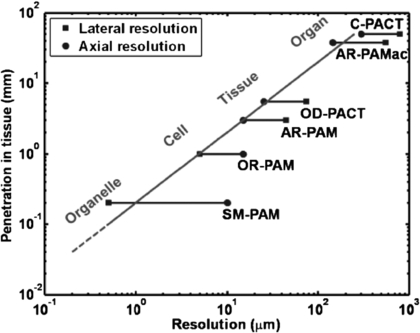

Download figure:

Standard image High-resolution image3.3.2. Applications, validation and comparison with other microvascular measurement techniques

Wang (2008) summarized the great potential for the technology, including melanoma detection, endoscopy, molecular imaging, gene expression, Doppler PT for flow measurement, metabolic rate measurements, mapping of sentinel lymph nodes, and breast and brain imaging. PT can be combined with other imaging modalities, including OCT, to enhance the information derived in microscopy (Li et al 2009), and also endoscopy. (Xi et al 2013). Xiang et al (2013) have advanced the 3D imaging and developed a 4D PT technique that generates motion pictures of imaged tissue, enabling real-time tracking of dynamic physiological and pathological processes at hundred micrometer-millisecond resolutions. The 4D PT technique was used to image needle-based drug delivery and study pharmacokinetics. It has also been suggested as a technique to monitor the fast haemodynamic changes during interictal periods in epilepsy and also the temperature variations during tumour thermal therapy.

Specific clinical studies include the identification of inflammatory arthritis and also breast cancer. Rajian et al (2012) used PT to identify neovascularity (angiogenesis) which is an early feature of inflammatory arthritis, thus giving an early diagnosis and facilitating treatment monitoring of the disease. A rat model was tested with imaging at two different wavelengths, 1064 and 532 nm, to reveal that there is a significant signal enhancement in the ankle joints of arthritis-affected rats when compared to a normal control group. Histology images obtained from both the normal and the arthritis-affected rats correlated well with the PT findings, supporting the view that PT could become a new tool for clinical management of inflammatory arthritis.

Manohar et al (2005, 2007) explored the utility of PT in breast cancer patients. Near-infrared photoacoustic images (figure 26) of ROI in four of the five cases of patients with symptomatic breasts revealed higher intensity regions attributed to vascular distribution associated with cancer. Of the two cases presented, one was especially significant, with benign indicators dominating in conventional radiological images, while photoacoustic images revealed vascular features suggestive of malignancy, corroborated by histopathology. The results showed that PT may have potential in visualizing certain breast cancers based on intrinsic optical absorption contrast. A future role for the approach could be in supplementing conventional breast imaging to assist detection and/or diagnosis. Improvements in contrast have been shown in a mouse tumour model by combining high-resolution near-infrared light-induced PT with NIR dye-labelled amino-terminal fragments of urokinase plasminogen activator receptor (uPAR) targeted magnetic iron oxide nanoparticles (NIR830-ATF-IONP) (Xi et al 2014). The accumulation of the targeted nanoparticles in the tumour led to photoacoustic contrast enhancement due to the high absorption of iron oxide nanoparticles (IONP). Near infrared fluorescence images were used to validate specific delivery of NIR830-ATF-IONP to mouse mammary tumours. Systemic delivery of the targeted IONP to the tumours produced a four-fold enhancement in photoacoustic signals compared to tumours that received non-targeted IONP. The use of targeted nanoparticles allowed imaging of tumours located deeper than 3 cm beneath healthy tissues. The study indicated that the combination of PT and receptor-targeted NIR830-ATF-IONP can provide improved specificity and sensitivity for breast cancer detection.

Figure 26. Invasive ductal carcinoma in the breast. (a) X-ray mammogram reveals abnormalities in architecture, (b) transverse sonographic scan image shows 17 mm irregular hypo-echoic solid mass, and (c) photoacoustic image reveals higher intensity regions attributed to tumour vascularization. Breast image obtained using 1064 nm laser excitation and ultrasound frequency of 1 MHz to give an imaging depth of approximately 2 cm and resolution of 2 mm. Image acquisition time was ∼30 min (permission granted to re-use from Manohar et al 2007 Opt. Express 15 12277–85).

Download figure: